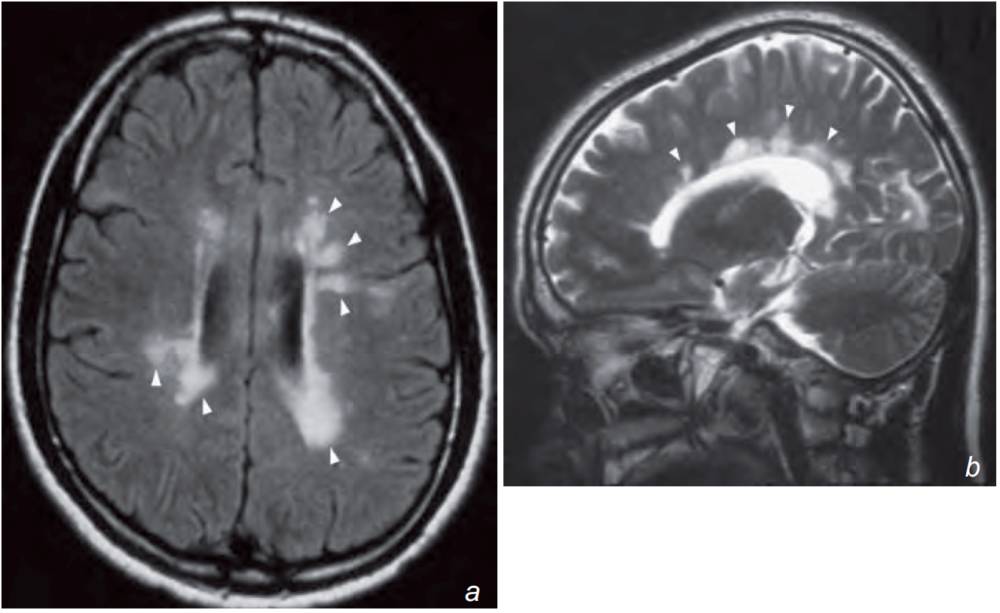

A 22-year-old woman with a previous history of optic neuritis two years earlier followed by multiple episodes of relapsing and remitting sensory and motor symptoms involving different parts of the body underwent MRI of the brain.

What does the MRI show and what is the most likely diagnosis?